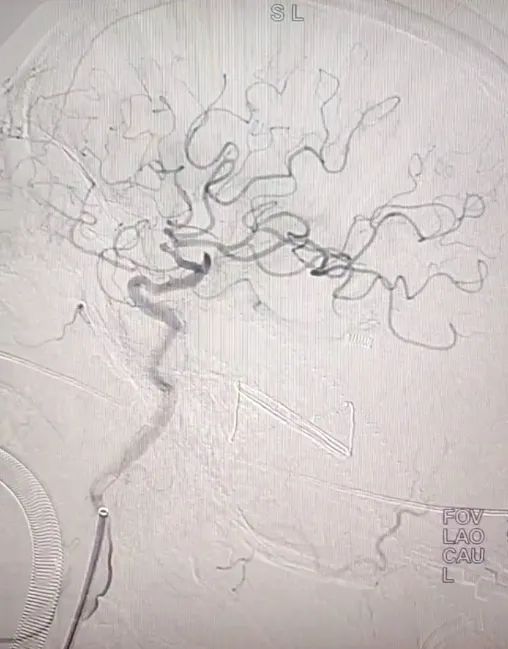

行“腦血管造影

經(jīng)皮顱內(nèi)動脈介入取栓術(shù)”

術(shù)中發(fā)現(xiàn)

李大爺左側(cè)頸

內(nèi)外頸動脈閉塞

左側(cè)大腦缺血嚴(yán)重

導(dǎo)管直達(dá)病變血管

抽吸取栓導(dǎo)管

無導(dǎo)絲順利入顱

通過負(fù)壓多次抽吸

血栓被一一“拿下”

為李大叔重新開通了閉塞血管

疏通了“生命之河”

從穿刺到再通

僅用25分鐘

極大的挽救了缺血的腦細(xì)胞

(上圖:取栓前)